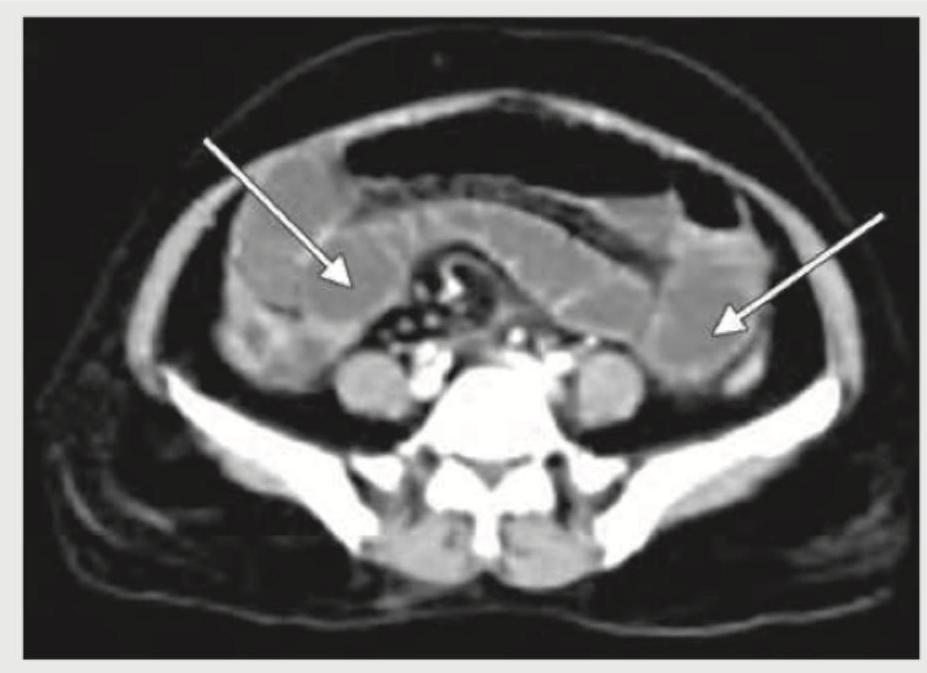

CECT abdomen of a patient with acute abdomen is given below. What is the diagnosis?

Explanation: ***Acute pancreatitis*** - The CECT image shows **peripancreatic fat stranding** and **fluid collection** (highlighted by the arrow), which are classic signs of acute pancreatitis. - The pancreas itself appears **enlarged** and **edematous** with areas of inflammatory changes. *Renal colic* - Renal colic typically presents with a **calculus (kidney stone)** in the ureter or renal pelvis, possibly with **hydronephrosis**. - No such features are visible in the provided image; the kidneys appear unremarkable. *PUD perforation* - A perforated peptic ulcer would show **free air under the diaphragm** on an upright chest X-ray or **free intra-abdominal air** on CT. - The image does not demonstrate any free intra-abdominal air, and the stomach and duodenum do not show signs of perforation. *Rectus sheath hematoma* - A rectus sheath hematoma would present as a **well-defined, high-density collection within the rectus abdominis muscle** or between the muscle and its sheath. - This image shows diffuse retroperitoneal inflammation and fluid collection, not confined to the rectus sheath.